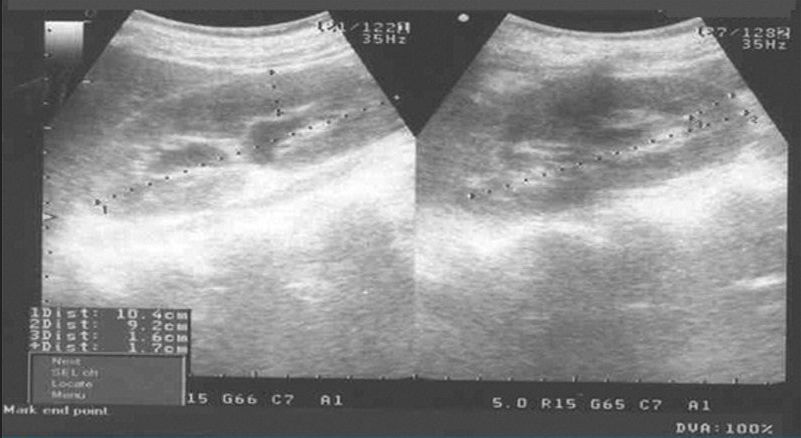

该患者的初步实验室检测显示,血红蛋白8mg/dL、红细胞沉降率(ESR)65mm/h、肝肾功能正常、尿液分析中红细胞(RBC)、白细胞(WBCs)和蛋白质阳性。胸部X线检查显示双侧胸腔积液(左侧更大)。Mantoux法皮肤测试为阴性。腹部和盆腔的超声检查显示双侧肾积水(图1)。

图1 腹部超声显示双侧肾积水

患者肠系膜和肠壁增厚,存在腹腔积液和中度腹水。用于分析的腹水样本显示渗出性腹水,以淋巴细胞为主(80%)。在细菌培养或革兰氏染色中未发现微生物,细胞学上未见恶性细胞。